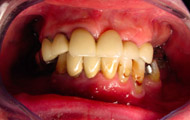

Exemple d’une réhabilitation complète implantaire

Situation clinique terminée